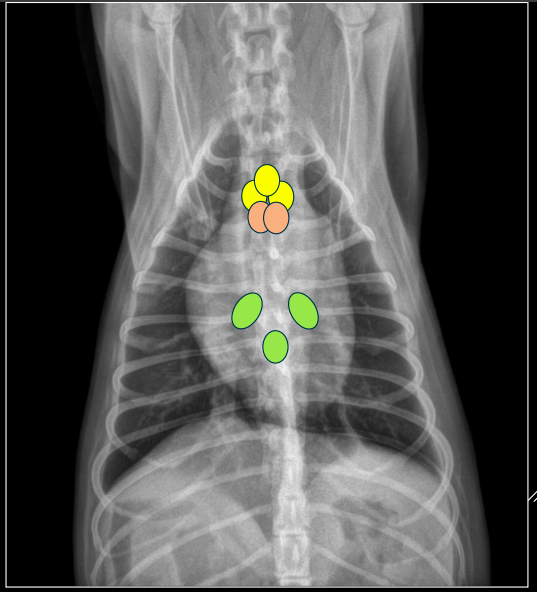

POSICIÓN DE CÁMARAS Y GRANDES VASOS (“analogía del reloj”)

Se puede comparar la silueta cardíaca con la esfera de un reloj <analogía del reloj=,utilizando los intervalos horarios para la localización de las cámaras cardíacas y de los grandes vasos.

Proyección DV:

- 11–1: arco aórtico.

- 1–2: arteria pulmonar.

- 2–3: orejuela AI.

- 3–5: ventrículo izdo.

- 5–9: ventrículo dcho.

- 9–11: aurícula dcha.

Proyección LL:

- Craneodorsal: aorta y atrio derecho.

- Craneoventral: ventrículo derecho.

- Caudodorsal: atrio izquierdo.

- Caudoventral: ventrículo izquierdo.